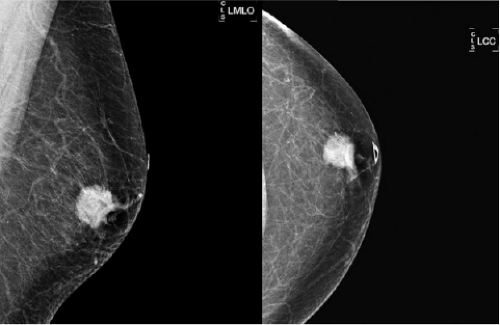

If the appearance is classic “flame shaped” on mammogram and there is NO evidence of a mass, then US should be avoided as this will usually lead to an unnecessary biopsy. US is indicated if the mammogram demonstrates a visible mass or the palpable breast mass is located away from the nipple (Fig. 19-3). Figure 19-4 demonstrates a left subareolar mass with convex borders and coarse calcifications on mammography. Calcifications seen on mammography deserve workup in the male breast. Magnification views should be performed to determine extent and

plan safe core biopsy. US of the area of calcifications is recommended, as this might facilitate a safer US-guided biopsy. A negative US should not dissuade one from sampling calcifications in the male breast as calcifications are frequently associated with ductal carcinoma in situ (DCIS). MRI of the breast offers little advantage other than assisting in ruling out chest-wall involvement.

![]() FIGURE 19-4 LEFT MLO and CC digital mammogram demonstrate a spiculated mass with calcifications in the retroareolar location. Note that no LEFT axillary nodes are seen on the LEFT MLO mammogram. |